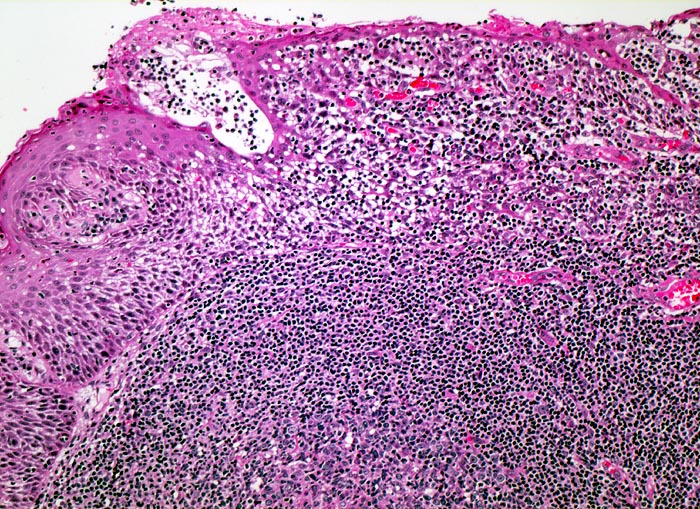

Tonsille mit Sekundärfollikel

Ein sekundärer Lymphfollikel mit angeschnittenem Keimzentrum wird bedeckt von Plattenepithel der Mundschleimhaut. Zahlreiche Lymphozyten infiltrieren das darüberliegende Epithel, was in der Tonsille ein Normalbefund darstellt.

100